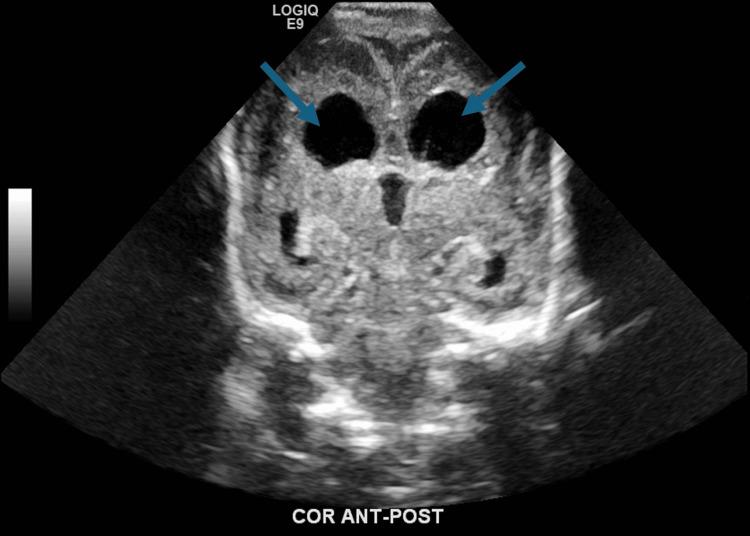

This case report investigates the management of a 24-week-old neonate with congenital cytomegalovirus (CMV) infection and its sequelae, including severe intrauterine growth restriction, thrombocytopenia, and brain anomalies, ultimately progressing to lissencephaly. The diagnostic challenges included delayed clinical suspicion of congenital CMV, which was not identified until after delivery through CMV DNA polymerase chain reaction, and differentiating its symptoms from other potential causes of the neonate's condition. Aggressive interventions included antibiotics, antiviral therapy with ganciclovir, and supportive measures such as intubation, CPR, respiratory support, blood transfusions, and management of coagulopathy. Despite these efforts, the patient deteriorated due to progressive hypoperfusion, hypoxemic cardiorespiratory failure, and disseminated intravascular coagulopathy. Due to the poor prognosis and extent of multiorgan damage, support was withdrawn per parental consent. This case highlights the complications encountered when managing an advanced-stage neonatal CMV infection and emphasizes the importance of a multidisciplinary and holistic approach to guide diagnosis and treatment.

本病例报告探讨了一名24周大先天性巨细胞病毒(CMV)感染新生儿及其后遗症的治疗情况,这些后遗症包括严重的宫内生长受限、血小板减少症和脑异常,最终发展为无脑回畸形。诊断面临的挑战包括先天性CMV的临床怀疑延迟,直到分娩后通过CMV DNA聚合酶链反应才得以确诊,以及将其症状与新生儿病情的其他潜在病因相区分。积极的干预措施包括使用抗生素、更昔洛韦抗病毒治疗,以及诸如插管、心肺复苏、呼吸支持、输血和凝血病管理等支持措施。尽管采取了这些措施,患者仍因进行性低灌注、低氧性心肺衰竭和弥散性血管内凝血而病情恶化。由于预后不良和多器官损伤程度严重,经家长同意停止了支持治疗。本病例突出了晚期新生儿CMV感染治疗中遇到的并发症,并强调了多学科整体方法在指导诊断和治疗方面的重要性。